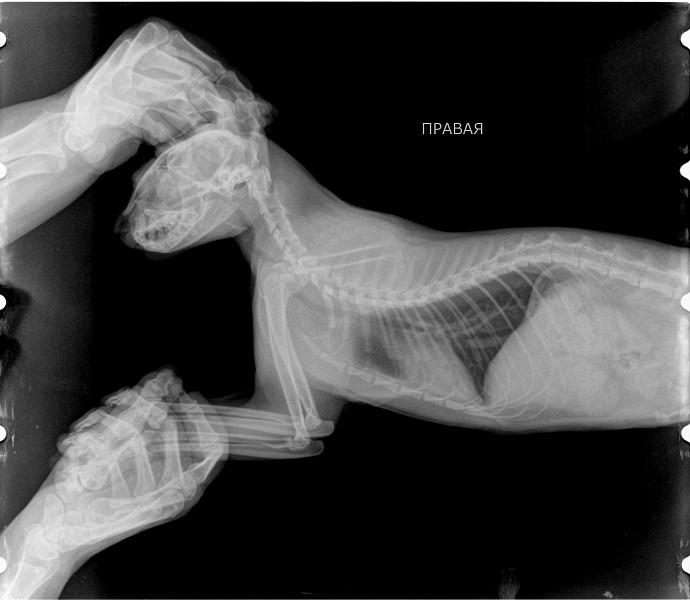

Рентгеновские снимки анатомии собак: строение и здоровье